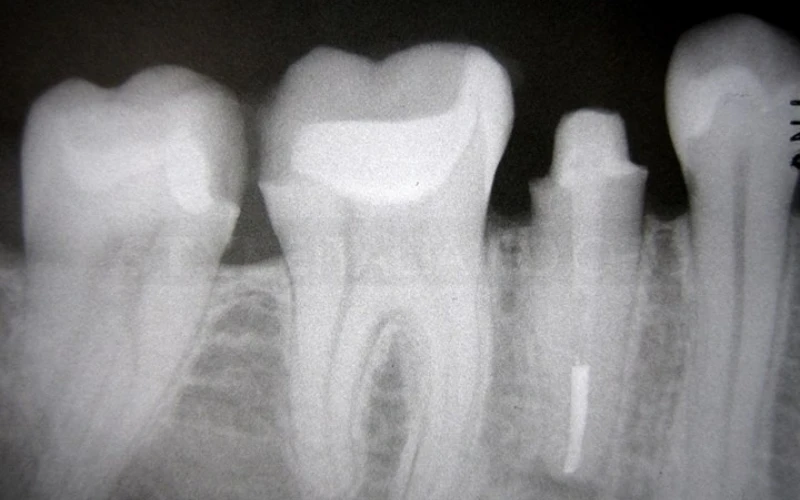

2. Phim cánh cắn cho thấy các răng nguyên nhân.

11. Chụp phim X-quang sau khi tái tạo để đánh giá khoảng sinh học và độ dày của phục hình inlay.

18. Phim cánh cắn sau điều trị. Tất cả các phục hình đều là composite, trực tiếp hoặc gián tiếp.